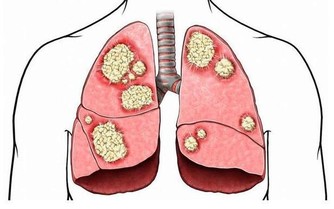

化膿性感染:主要為金黃色葡萄球菌、鏈球菌等感染毛囊引起的癤、癰,此病會此起彼伏反復發作,如果一味地治皮膚病,忽視血糖的控制,極易發展為敗血症而危及生命。

真菌感染:有毛癬菌所致的股癬、甲癬、足癬和手癬;有念珠球菌所致的口炎、陰道炎、巴氏腺炎,同樣也是好好壞壞難以根治。